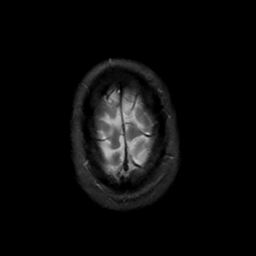

MR Study #3, February 24, 1991 -- Slice #46

[Home][Help][Clinical][Tour 1][Tour 2] Slice 46